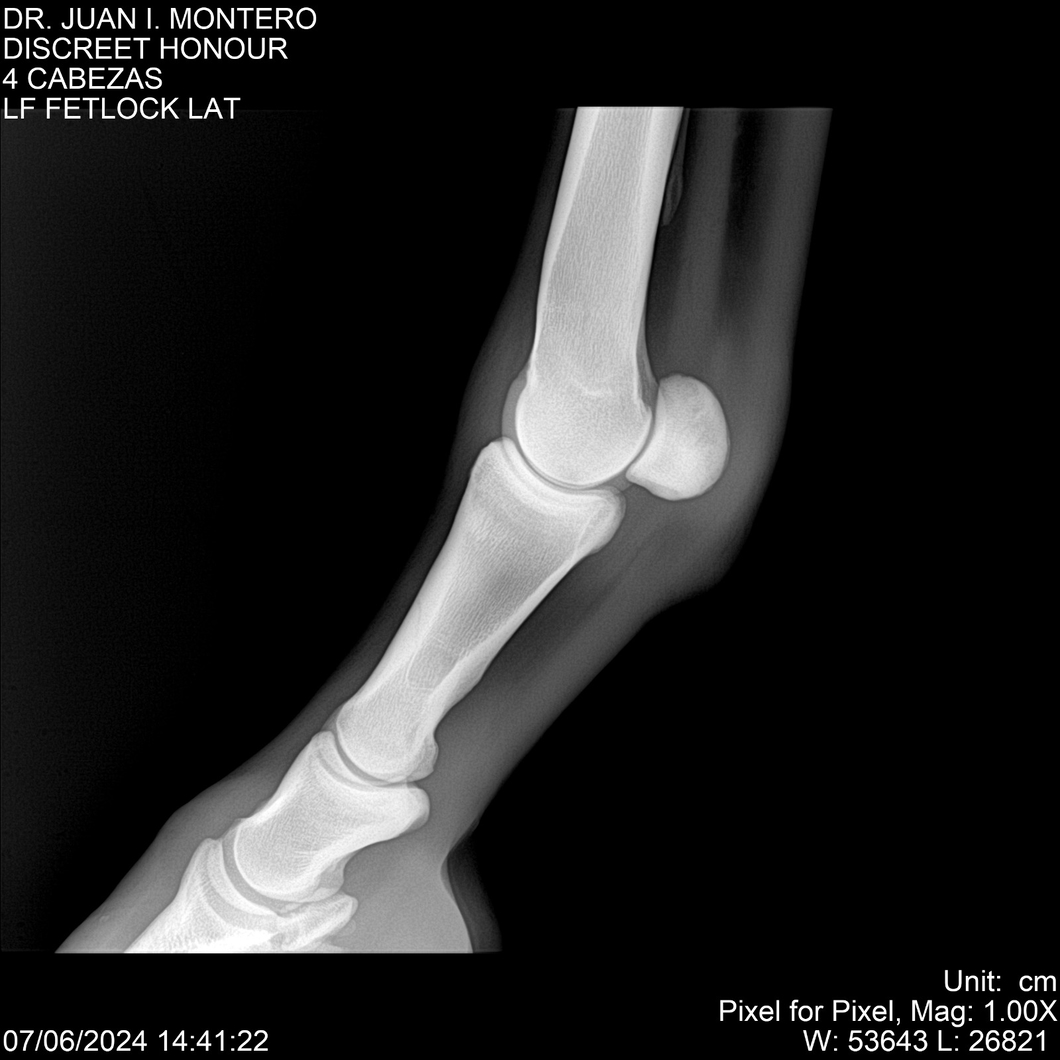

LOTE 6, DISCREET HONOUR 🔥 🔥 🔥 Lote Anterior Volver al remate Lote Siguiente Ficha Contacto Montevideo - Ficha del Lote Identificador: #281093 Categoría: Yeguarizos Montevideo - 82 Visualizaciones ClicData Contacto Empresa: Abelenda N. R., Walter Hugo Nombre*: Teléfono* : E-mail* : Mensaje Enviar Registrese gratis Este contenido Exclusivo está disponible sólo para usuarios registrados Ingresar